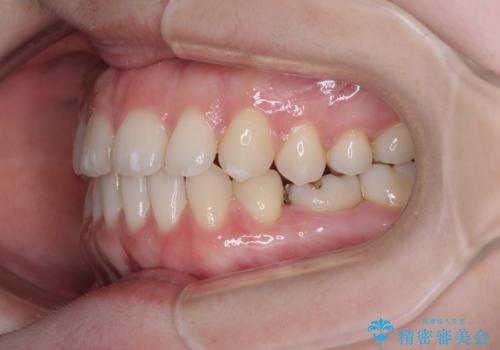

すきっ歯をインビザラインできれいな歯並びに改善

- 1年5ヶ月

- 前歯の隙間を気にして来院された患者様です。

隙間や叢生の程度はそれほど著しいものではなかったので、インビザラインでもワイヤー矯正でも対応可能でしたが、極力目立たない装置を希望されたため、インビザラインにて矯正治療を行うこととしました。

すきっ歯の原因は色々ありますが、嚥下や発音時の舌突出癖が大きな原因となることがあります。

こちらの患者様も強い突出癖があったため、舌のトレーニング指導を行いました。